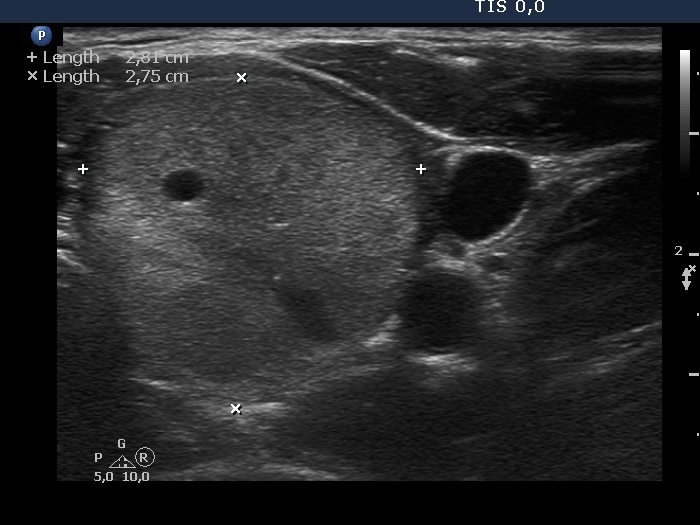

Ethanol sclerotherapy: non-toxic solid nodules - Case 5

Fourteen years after the therapy (ultrasonographic picture 5)

Middle part of the left lobe, horizontal scan. This part of the treated nodule has increased in size.